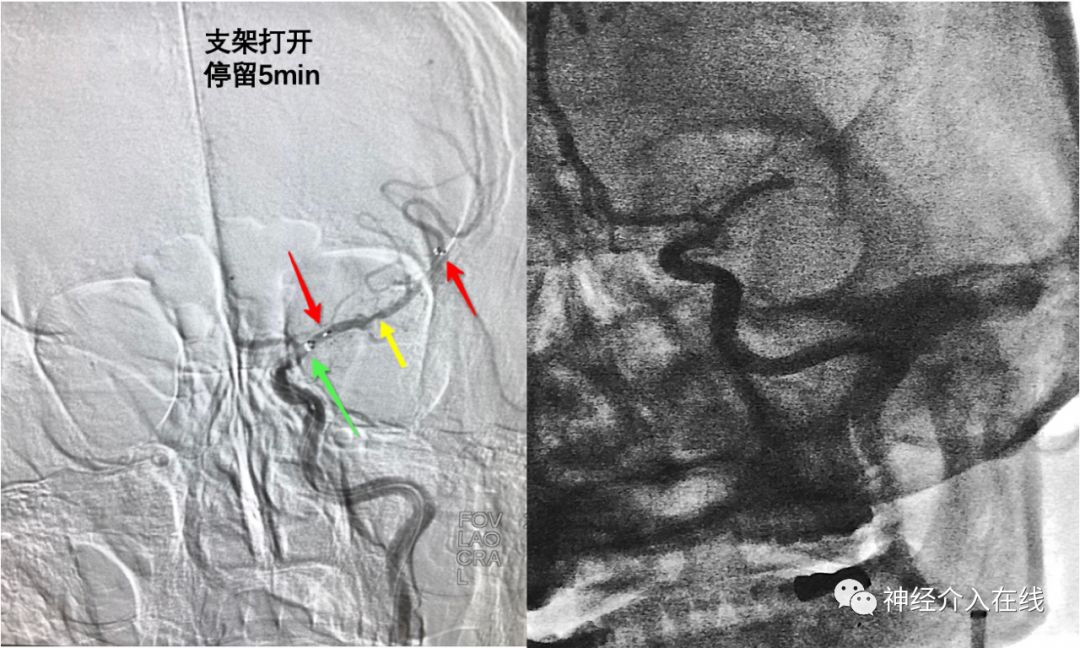

术中取栓过程:6F长鞘支撑,5F Sofia裸奔到M1段闭塞处,50ml注射器持续抽吸失败,遂经微导管送入Reco 4*20mm支架,支架打开血流即刻恢复,停留5min,将Sofia(绿箭)推过大脑前连同Reco(红箭)一起回撤出长鞘,造影见LMCA闭塞未通,多次冲洗支架和Sofia管腔也未见血栓,心塞!

返回看支架停留的影像,难道合并ICAS(黄箭),开始怀疑人生啦,感觉抽吸+取栓策略是对头滴,打算再来SWIM(Sofia+Reco山寨版)一把。第二把,完全再通,mTICI 3级。仔细想想患者LMCA 并不是狭窄(黄箭),仅是支架在血栓内未充分打开。